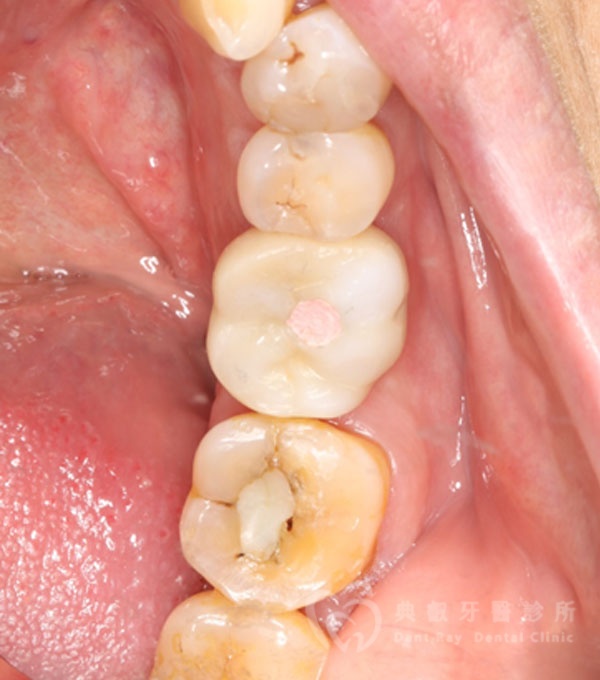

植牙案例一